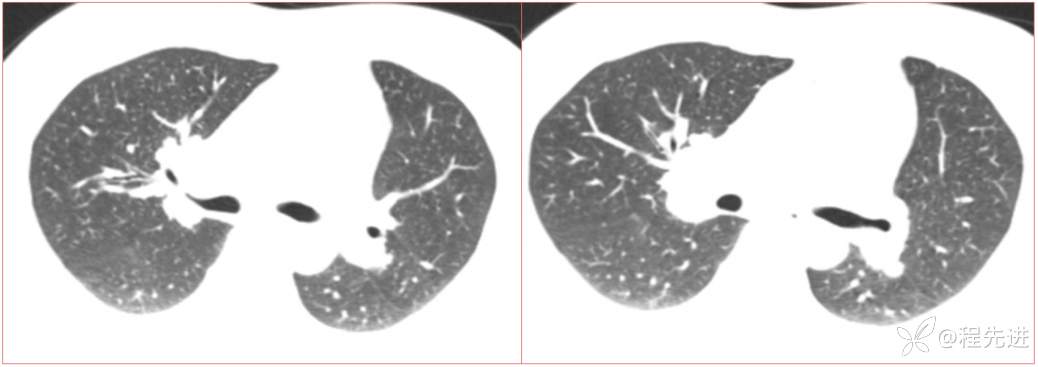

简要病史:患者一周前无明显诱因出现阵发性刺激性咳嗽,咳少量白色粘液痰,咳嗽无明显昼夜节律性,无发热、畏冷、寒战,无头痛、胸闷、胸痛,自行服药后 (具体不详) 症状无缓解,3天前外院胸片检查示右上病变

辅助检查:肺肿瘤标志物:神经元特异性烯醇化酶(NSE):35.72ng/ml(参考值0-16.3);非小细胞肺癌相关抗原211、胚抗原糖类抗原125、铁蛋白、鳞状细胞癌抗原未见异常